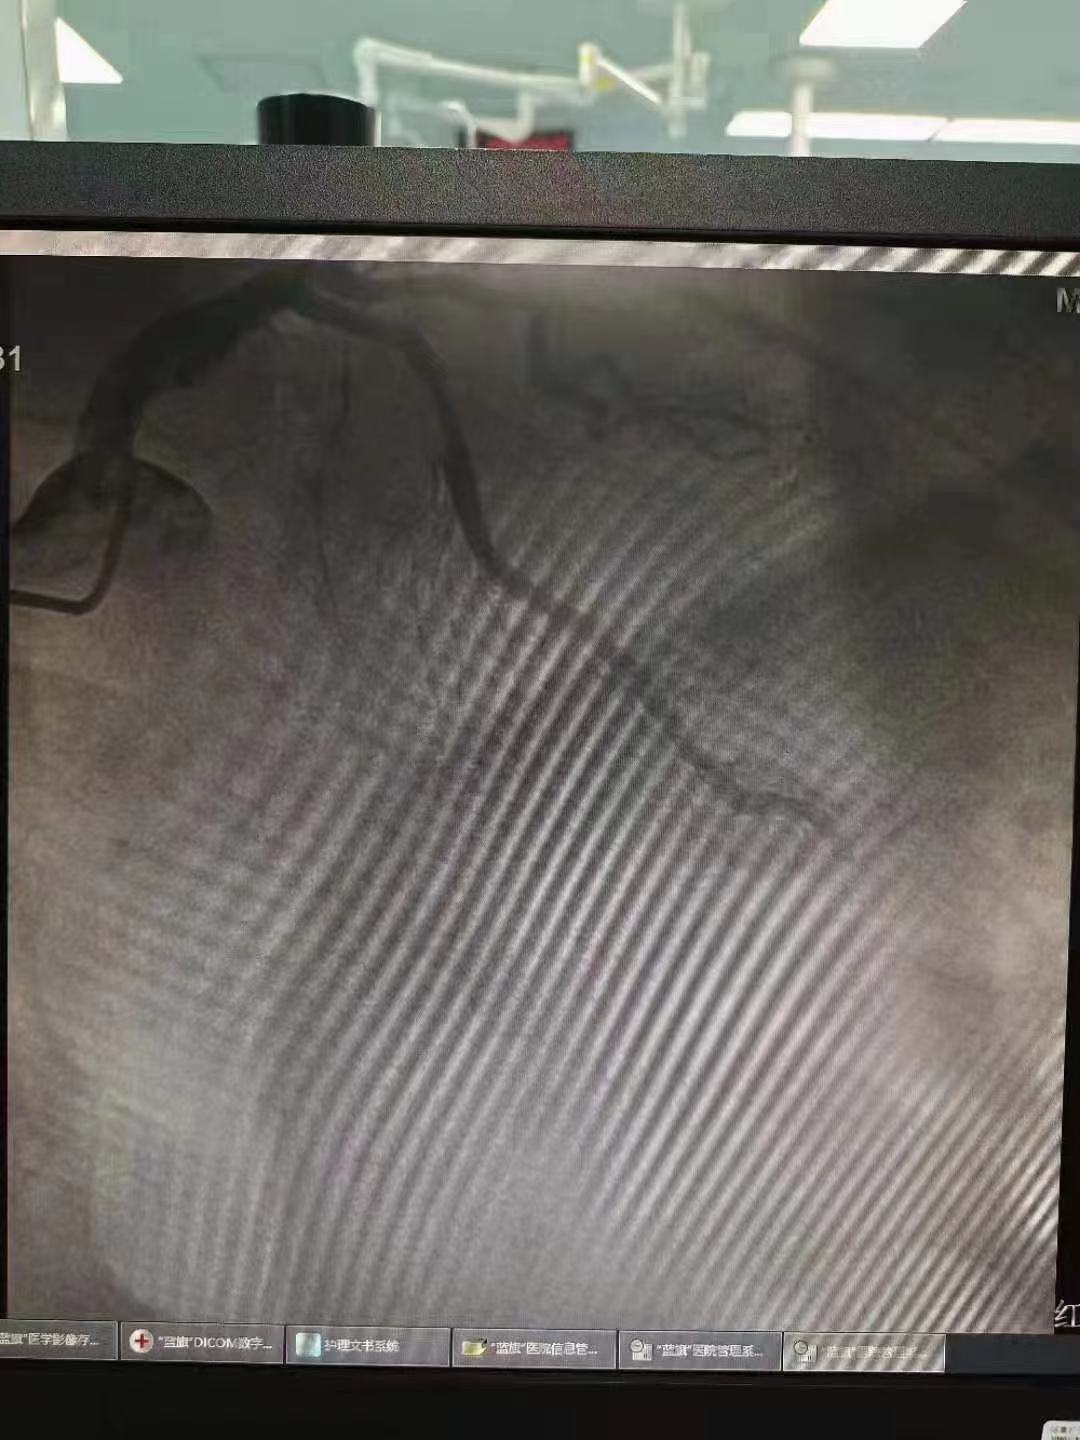

祝賀 云南省滇南中心醫(yī)院  黃銳團隊成功為患者植入3.5~15Xinsorb生物可吸收支架!